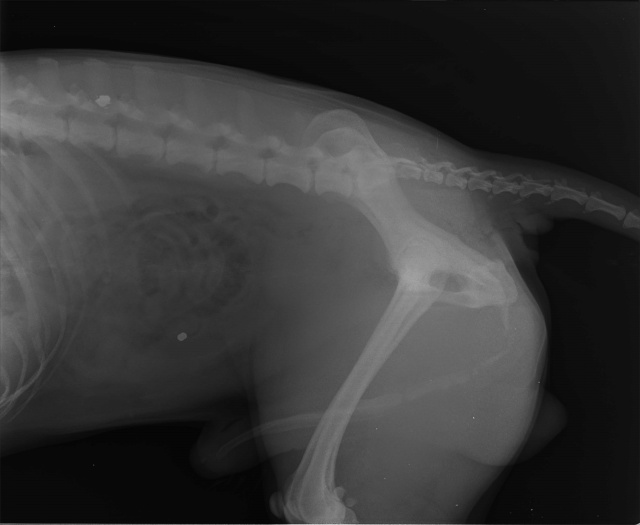

16530 - Maardu/ TONY

- Возраст: 10 лет

Vigastatud. Tulistatud õhupüssist, üks kuul kõhu sees ja teine selgroos.